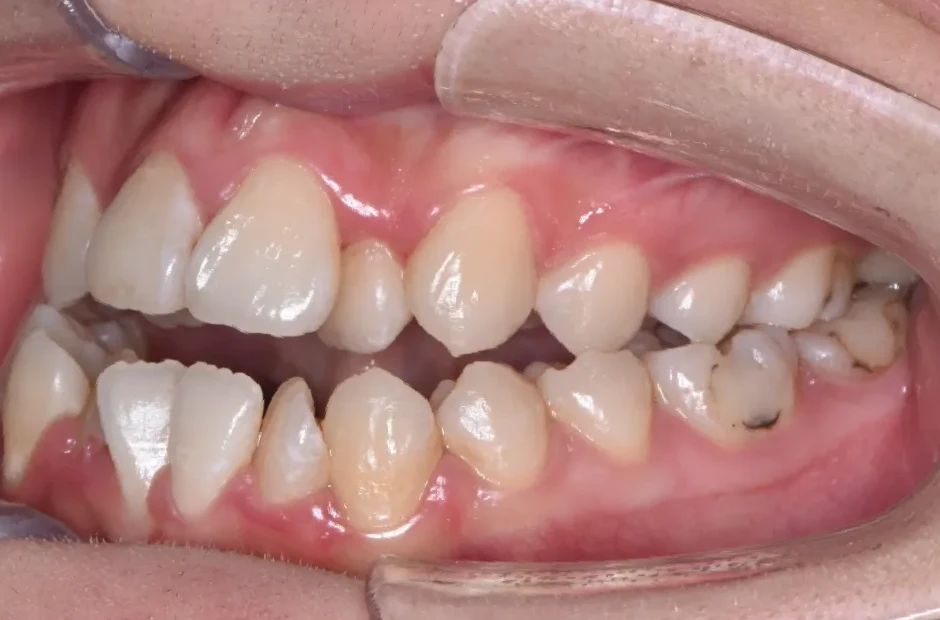

八重歯・でこぼこ・乱ぐい歯

(叢生)

歯が並ぶスペースが足りないために、歯が重なったり前後にずれて生えていたりする状態です。犬歯(八重歯)など目立つ部分の歯列が乱れている場合は、口元の印象に悪影響を与えます。原因としては、遺伝や乳歯の早期抜歯、顎の成長不足などがあげられます。歯磨きが不十分になりやすく、虫歯や歯周病のリスクが高まりやすい不正咬合です。矯正治療を受けると、見た目がよくなるだけでなく清掃性が高まり、お口の健康を維持しやすくなります。

| 診断名・主訴 | 下顎前突、叢生 |

|---|---|

| 年齢・性別 | 23歳・女性 |

| 治療期間・回数 | 3年 |

| 治療に用いた主な装置 | 上顎5,5 下顎4,4 |

| 抜歯部位 | 舌側矯正 |

| 治療費 | 100万円(税抜) |

| リスク・副作用 | 装置による違和感・疼痛・歯肉退縮・歯根吸収・虫歯のリスクなど |

治療前